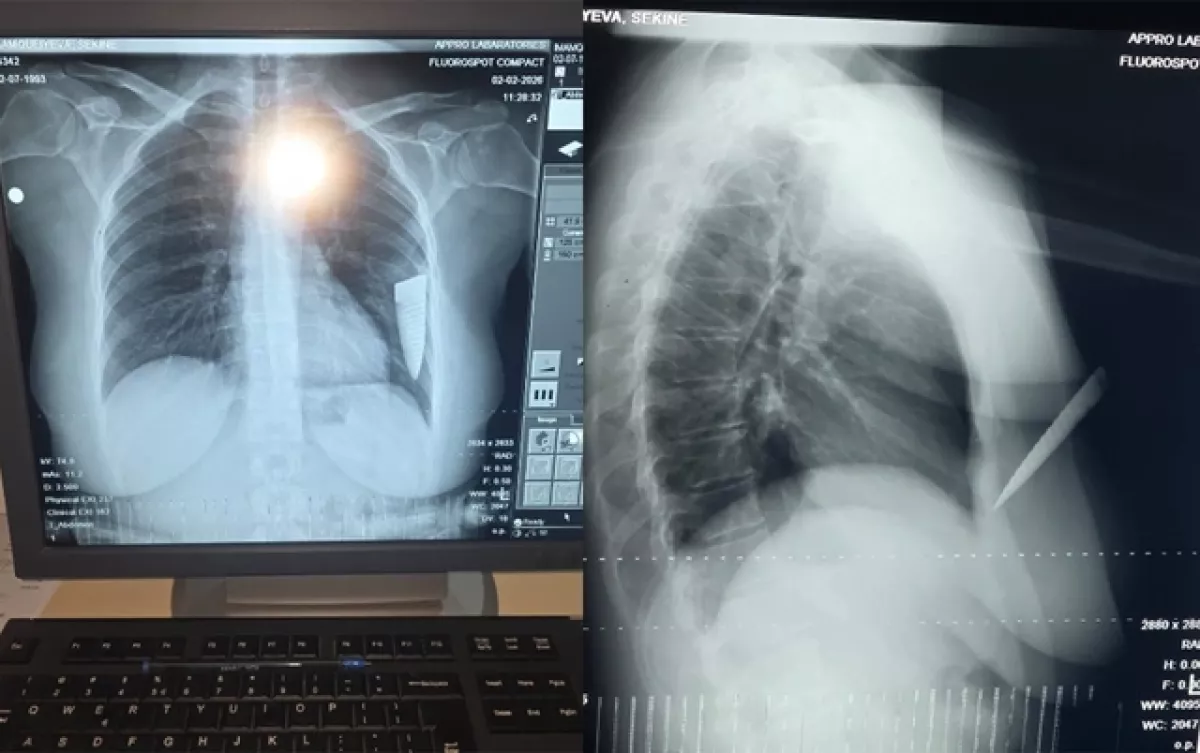

«1 февраля около 19:00, когда я выходила из дома торжеств в Шамкире, на меня внезапно напал Али Аскеров, с которым я раньше состояла в неофициальных отношениях. Он подошел к автомобилю, открыл переднюю правую дверь и начал меня душить, схватив за горло. Затем он достал из кармана нож и нанес мне 4 удара. Один удар пришелся в грудь, остальные три - в левую руку. Затем лезвие ножа сломалось и осталось у меня в грудной клетке. Если бы не это, он мог бы нанести еще больше ударов и убить меня, так как бил ножом непрерывно. Увидев, что нож сломался, а на шум сбегаются люди, Али скрылся с места происшествия», - сообщила пострадавшая.

По словам С.Имамгулиевой, причиной инцидента стало ее расставание с возлюбленным: «Нашим отношениям пришел конец. Али после расставания регулярно преследовал меня и угрожал. После того как он нанес мне ножевое ранение, меня доставили в Центральную районную больницу, а оттуда - в госпиталь в Гяндже, где прооперировали. Часть ножа, сломавшаяся и оставшаяся в моей грудной клетке, была удалена при хирургической операции. В настоящее время из-за серьезных осложнений со здоровьем я не могу работать. В результате инцидента я понесла материальный и моральный ущерб, а противоположная сторона даже не интересуется моим состоянием».